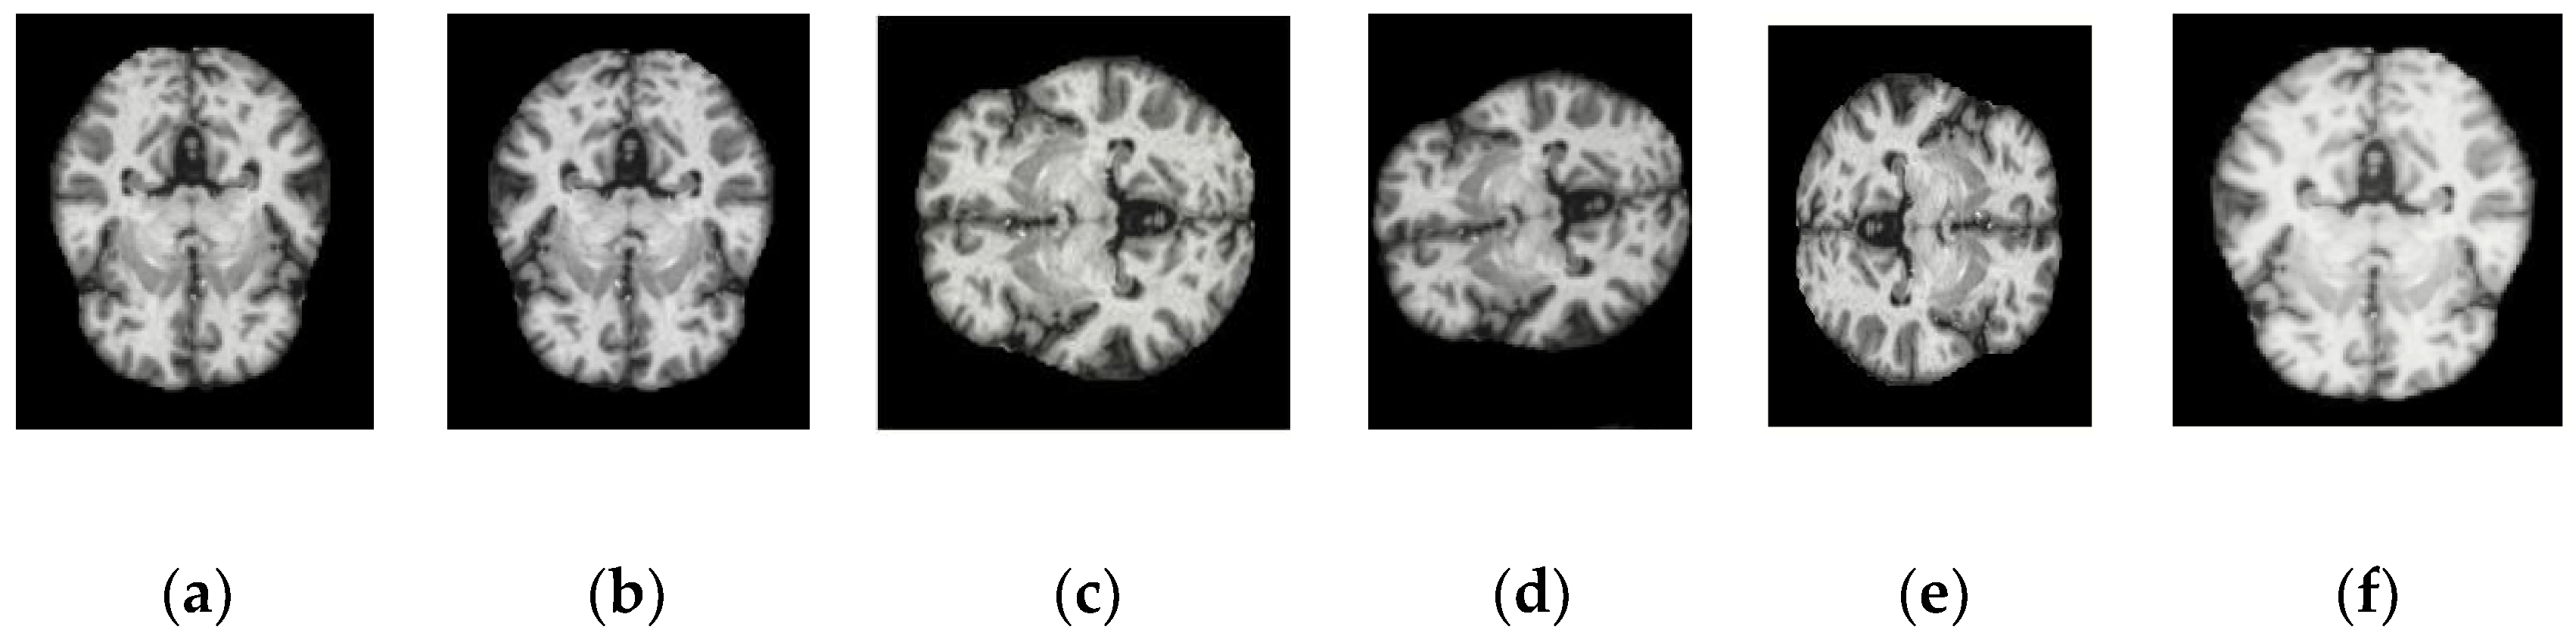

| Conv_1 | ![]() | ![]() | ![]() | ![]() |

| Conv_2 | ![]() | ![]() | ![]() | ![]() |

| Conv_3 | ![]() | ![]() | ![]() | ![]() |

| Conv_4 | ![]() | ![]() | ![]() | ![]() |

| Conv_5 | ![]() | ![]() | ![]() | ![]() |